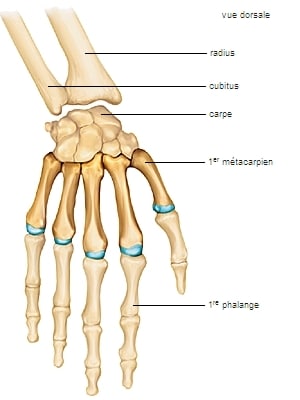

Composée de 27 os, animée par de nombreux tendons et muscles commandés par des nerfs, l’anatomie complexe de la main permet une grande palette d’actions. Outil essentiel de l’homme, la main est exposée à de nombreux risques d’accidents domestiques, professionnels et sportifs. La préhension associant force et dextérité expose avec le temps la main à des tendinites ainsi qu'à des pathologies dégénératives (arthrose).

Exposée facilement au traumatisme, la main est fréquemment le siège de fractures au niveau des métacarpiens ou des phalanges. Pour les os du carpe voir la rubrique “Poignet”.

Anatomie de la main